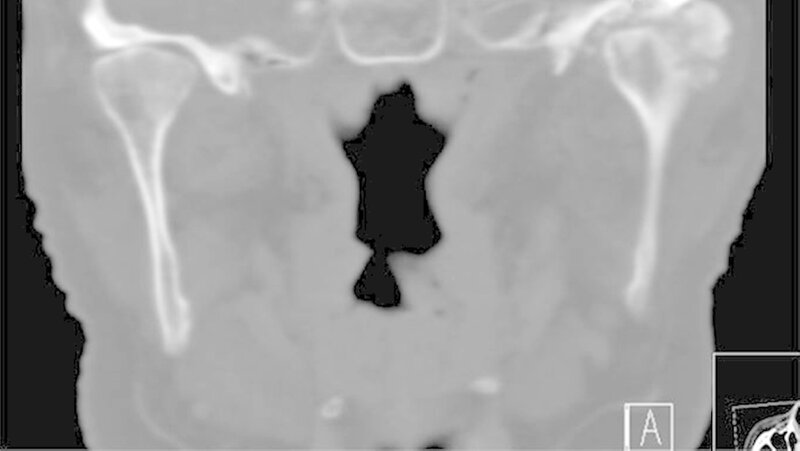

Die klinische Untersuchung zeigte eine überwärmte, schmerzhafte Schwellung präauriculär links und eine stark eingeschränkte Mundöffnung bei zahnlosem Kiefer. Das angefertigte Orthopantomogramm und die Schädelaufnahme in posterior-anteriorer Projektion gaben keinen eindeutigen Hinweis auf Pathologien im Bereich des linken Kiefergelenks, mit denen die ausgeprägten Beschwerden der Patientin hätten erklärt werden können.

Es war lediglich ein stark verschmälerter Gelenkspalt im Bereich des linken Kiefergelenks erkennbar, woraufhin eine Computertomografie des Unterkiefers durchgeführt wurde (Abbildungen 1 und 2). Dabei zeigten sich eine Deformierung des linken Kiefergelenksköpfchens mit Unregelmäßigkeiten der Kortikalis sowie eine Fremdkörpereinlagerung (freie Gelenkkörperchen) im Bereich des Gelenkspalts (Abbildungen 3 und 4).